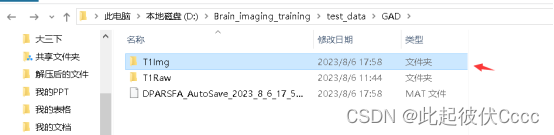

在与T1Raw相同文件夹的T1Img文件中生成了图像格式转换后的.nii文件,如下图所示: